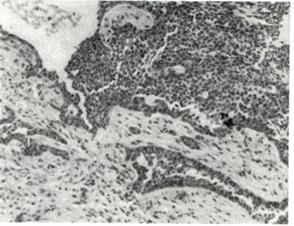

АдамантиномаАдамантинома (adamantinoma; греческое adamas, adamantos—твердый металл + -oma; синонимы: адамантобластома, амелобластома) — эпителиальная доброкачественная опухоль, в которой формируются структуры, напоминающие эмалевый орган закладки зуба. Встречается сравнительно редко; возникает адамантинома чаще в толще нижней челюсти в области угла на уровне моляров, значительно реже — в верхней челюсти, в единичных случаях — в большеберцовой кости, а также в гипофизе и яичниках. Макроскопически различают две формы адамантиномы — солидную (adamantinoma solidum) и поликистозную (adamantinoma polycysticum). Эти две формы опухоли не являются самостоятельными. Солидная форма — более ранняя стадия развития опухоли, чаще наблюдается в верхней челюсти и растет быстрее, чем поликистозная. На разрезе солидная адамантинома представляет собой узел мягковатой или плотноватой консистенции грязно-серого или красноватого цвета, капсула может отсутствовать. Поликистозная форма адамантиномы характеризуется наличием нескольких кист. Кисты выполнены светлой или бурой жидкостью различной консистенции. При микроскопическом исследовании (Рис. 1.) выявляются характерные разветвляющиеся эпителиальные тяжи или округлые участки, между которыми проходят соединительнотканные прослойки, содержащие кровеносные и лимфотические, сосуды. До периферии этих эпителиальных комплексов располагаются в один ряд высокие цилиндрические клетки с крупными ядрами, за которыми следуют кубические и полигональные клетки. В центре эпителиальных комплексов расположены звездчатые клетки. Указанная картина сходна со строением развивающегося эмалевого органа зуба.